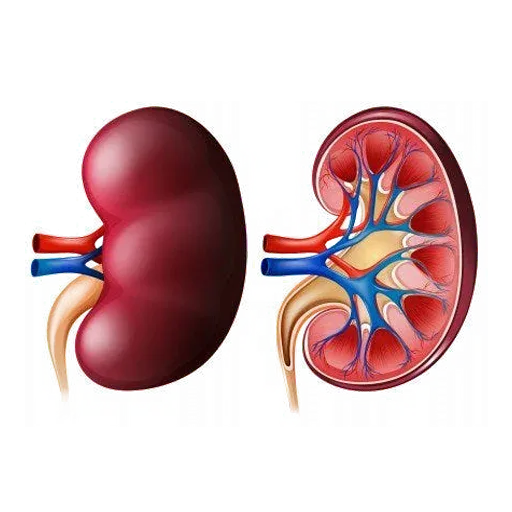

Complete Treatment for Stage 1-5 & Kidney Dialysis

Our Complete Treatment for Kidney Dialysis Kit is a holistic Ayurvedic solution designed to support kidney health and enhance overall well-being. Available in three convenient packages—365 days, 243 days, and 182 days—this treatment provides a blend of potent Ayurvedic medicines and herbal formulations known for their diuretic, antioxidant, and anti-inflammatory properties. The kit works synergistically to promote detoxification, enhance blood filtration, maintain fluid and electrolyte balance, and reduce inflammation, supporting the kidneys’ natural functions. Carefully crafted to address the challenges of dialysis, this kit offers a safe, effective, and sustainable approach to improving kidney health and reducing dependency on external interventions.

Ayurveda utilizes specific herbs and herbal formulations that are believed to benefit kidney health. These herbs, such as Punarnava, Gokshura, and Varunadi Kwath, are often used for their diuretic, anti-inflammatory, and antioxidant properties. They may help flush toxins, reduce inflammation, and support the kidneys’ overall function.

Kaknee Specialty:

- Filtration of Blood

- Maintaining Fluid and Electrolyte Balance

- Regulation of Blood Pressure

- Regulation of Erythropoiesis

- Maintaining Acid-Base Balance

- Metabolism of Vitamin D

- Detoxification

- Glucose Regulation

- Supporting the Immune System

- Maintaining Overall Homeostasis

We, “Medilux Lifecare”, are a highly reputable Ayurvedic brand providing ayurvedic treatment for kidney infections alongside various lifestyle disorders worldwide. We utilize 100% ayurvedic herbs for kidney issues, respiratory concerns, gastrointestinal problems, and numerous other ailments at Medilux Lifecare Hospital, complemented by a well-balanced diet for our patients. The patient is deeply valued for the personalized approach in Panchakarma treatment, compassionate care, and round-the-clock support from our highly qualified health counselors and doctors. Medilux Lifecare’s ayurvedic kidney treatment plan aids in enhancing the physical well-being and medical reports of patients (including the GFR level of the kidney). In addition to merely managing kidney disease with ayurvedic methods, our ayurvedic doctors are proficient in addressing a wide range of disorders and illnesses.